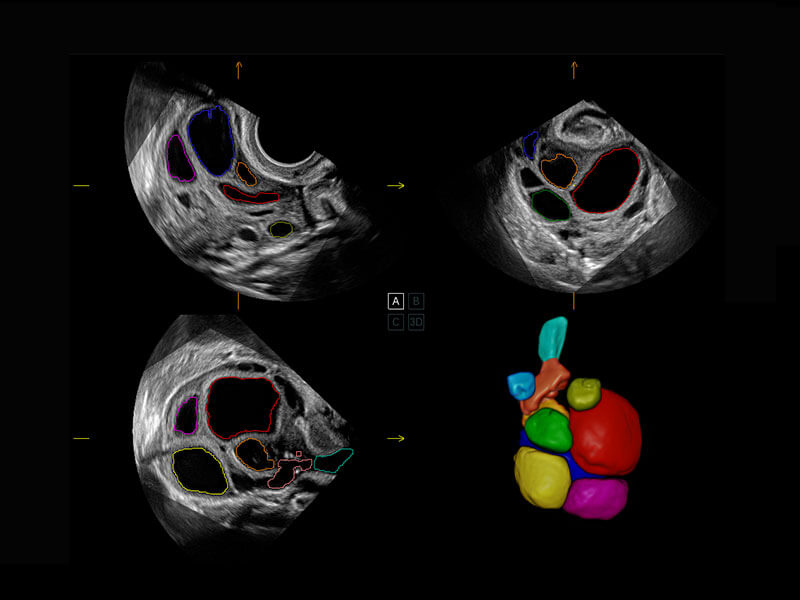

胎心容积成像

P60搭载一系列胎儿心脏成像技术,实现精细的胎儿心脏评估。